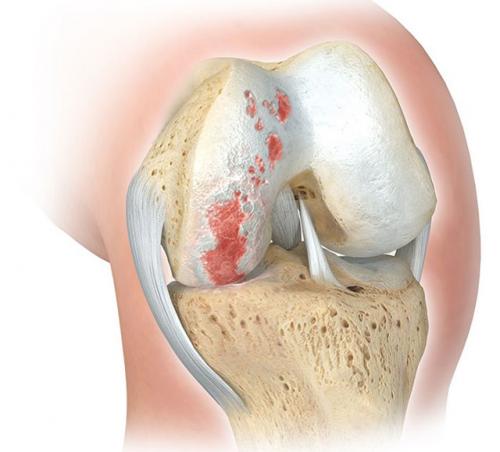

- дегенеративно-дистрофические. Чаще встречаются у пожилых людей и лиц, которые постоянно выполняют тяжелую физическую работу. Дегенеративные процессыэто следствие старения организма, которое сопровождается замедлением метаболизма и кровообращения в суставах. Под действием провоцирующих факторов (физические нагрузки, нехватка кальция, обменные нарушения) суставные хрящи начинают разрушаться, что приводит к развитию патологии. Дегенеративно-дистрофические заболевания имеют хроническое, медленно прогрессирующее течение;

Большеберцовая кость расположена на голени медиально (с внутренней стороны) и, как и бедренная кость, имеет два мыщелка: латеральный и медиальный, а между ними небольшое поднятие – межмыщелковое возвышение. Поверхность мыщелков большеберцовой кости практически плоская, лишь с небольшой вогнутостью, тогда как мыщелки бедренной кости заметно более выпуклые. Из-за этого возникает небольшое несоответствие суставных поверхностей, которое корректируется наличием особых хрящевых прокладок – менисков. Их в коленном суставе также два: латеральный и медиальный. Верхние их поверхности соответствуют по форме мыщелкам бедренной кости, а нижние – мыщелкам большеберцовой кости.

Медиальный мениск узким кольцом охватывает суставные поверхности медиальных мыщелков, латеральный мениск прикрывает большую часть суставной поверхности латерального мениска большеберцовой кости. Прикрепляются мениски коленного сустава к межмыщелковому возвышению большеберцовой кости. Между собой мениски соединяются поперечной связкой голени. Основная функция менисков – амортизация при движении костей коленного сустава относительно друг друга.